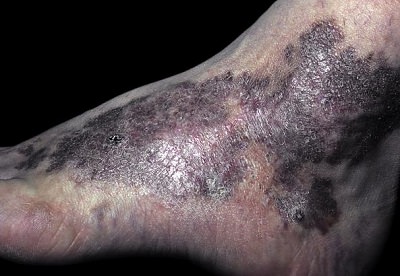

1. Klasik Kaposi Sarkomu

Bu formu genellikle el, ayak ve bacakların üst kısımlarında görülür. Lezyonlar zamanla yukarıya (proksimale) doğru yayılma eğilimindedir. Morumsu makül veya papül ve plaklarla başlayan lezyonlar, daha sonra nodüllere dönüşür. Doğu Avrupa ve Akdeniz ülkelerinde, özellikle yaşlı erkeklerde (erkek/kadın oranı 15/1) sık gözlenir. Yaşlı hastalarda hastalığın ilerleyişi daha yavaştır ve genellikle iyi huylu bir klinik seyir gösterir. Bu tipte mukozal tutulum nadirdir.

Tanısı, klinik bulgular ve deri biyopsilerindeki histopatolojik inceleme ile konulur. Tedavide; cerrahi, lazer, elektrocerrahi ve tek lezyonlarda IL interferon alfa-2b (1-3 milyon ünite) etkilidir.